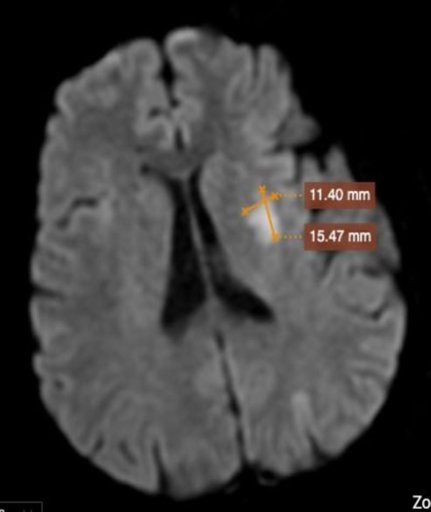

Đột ngột mất ngôn ngữ, run và yếu tay chân, không thể cầm nắm, đi lại, nữ bệnh nhân tới cấp cứu tại Bệnh viện Đa khoa MEDLATEC và được chẩn đoán đột quỵ não. Nhờ được cấp cứu kịp thời trong giờ “vàng”, bà H. may mắn thoát cửa tử.

Đột quỵ não là gì? Những lưu ý bạn cần biết về đột quỵ não

Đột quỵ não hay tai biến mạch máu não là một trong những căn bệnh đe dọa trực tiếp tới sức khỏe và tính mạng của con người. Ngày càng có nhiều trường hợp tử vong do đột quỵ não, vì thế mà bạn cần nắm những biểu hiện của bệnh để có phương án cấp cứu và chữa trị kịp thời. Vậy đột quỵ não là gì? Tại...